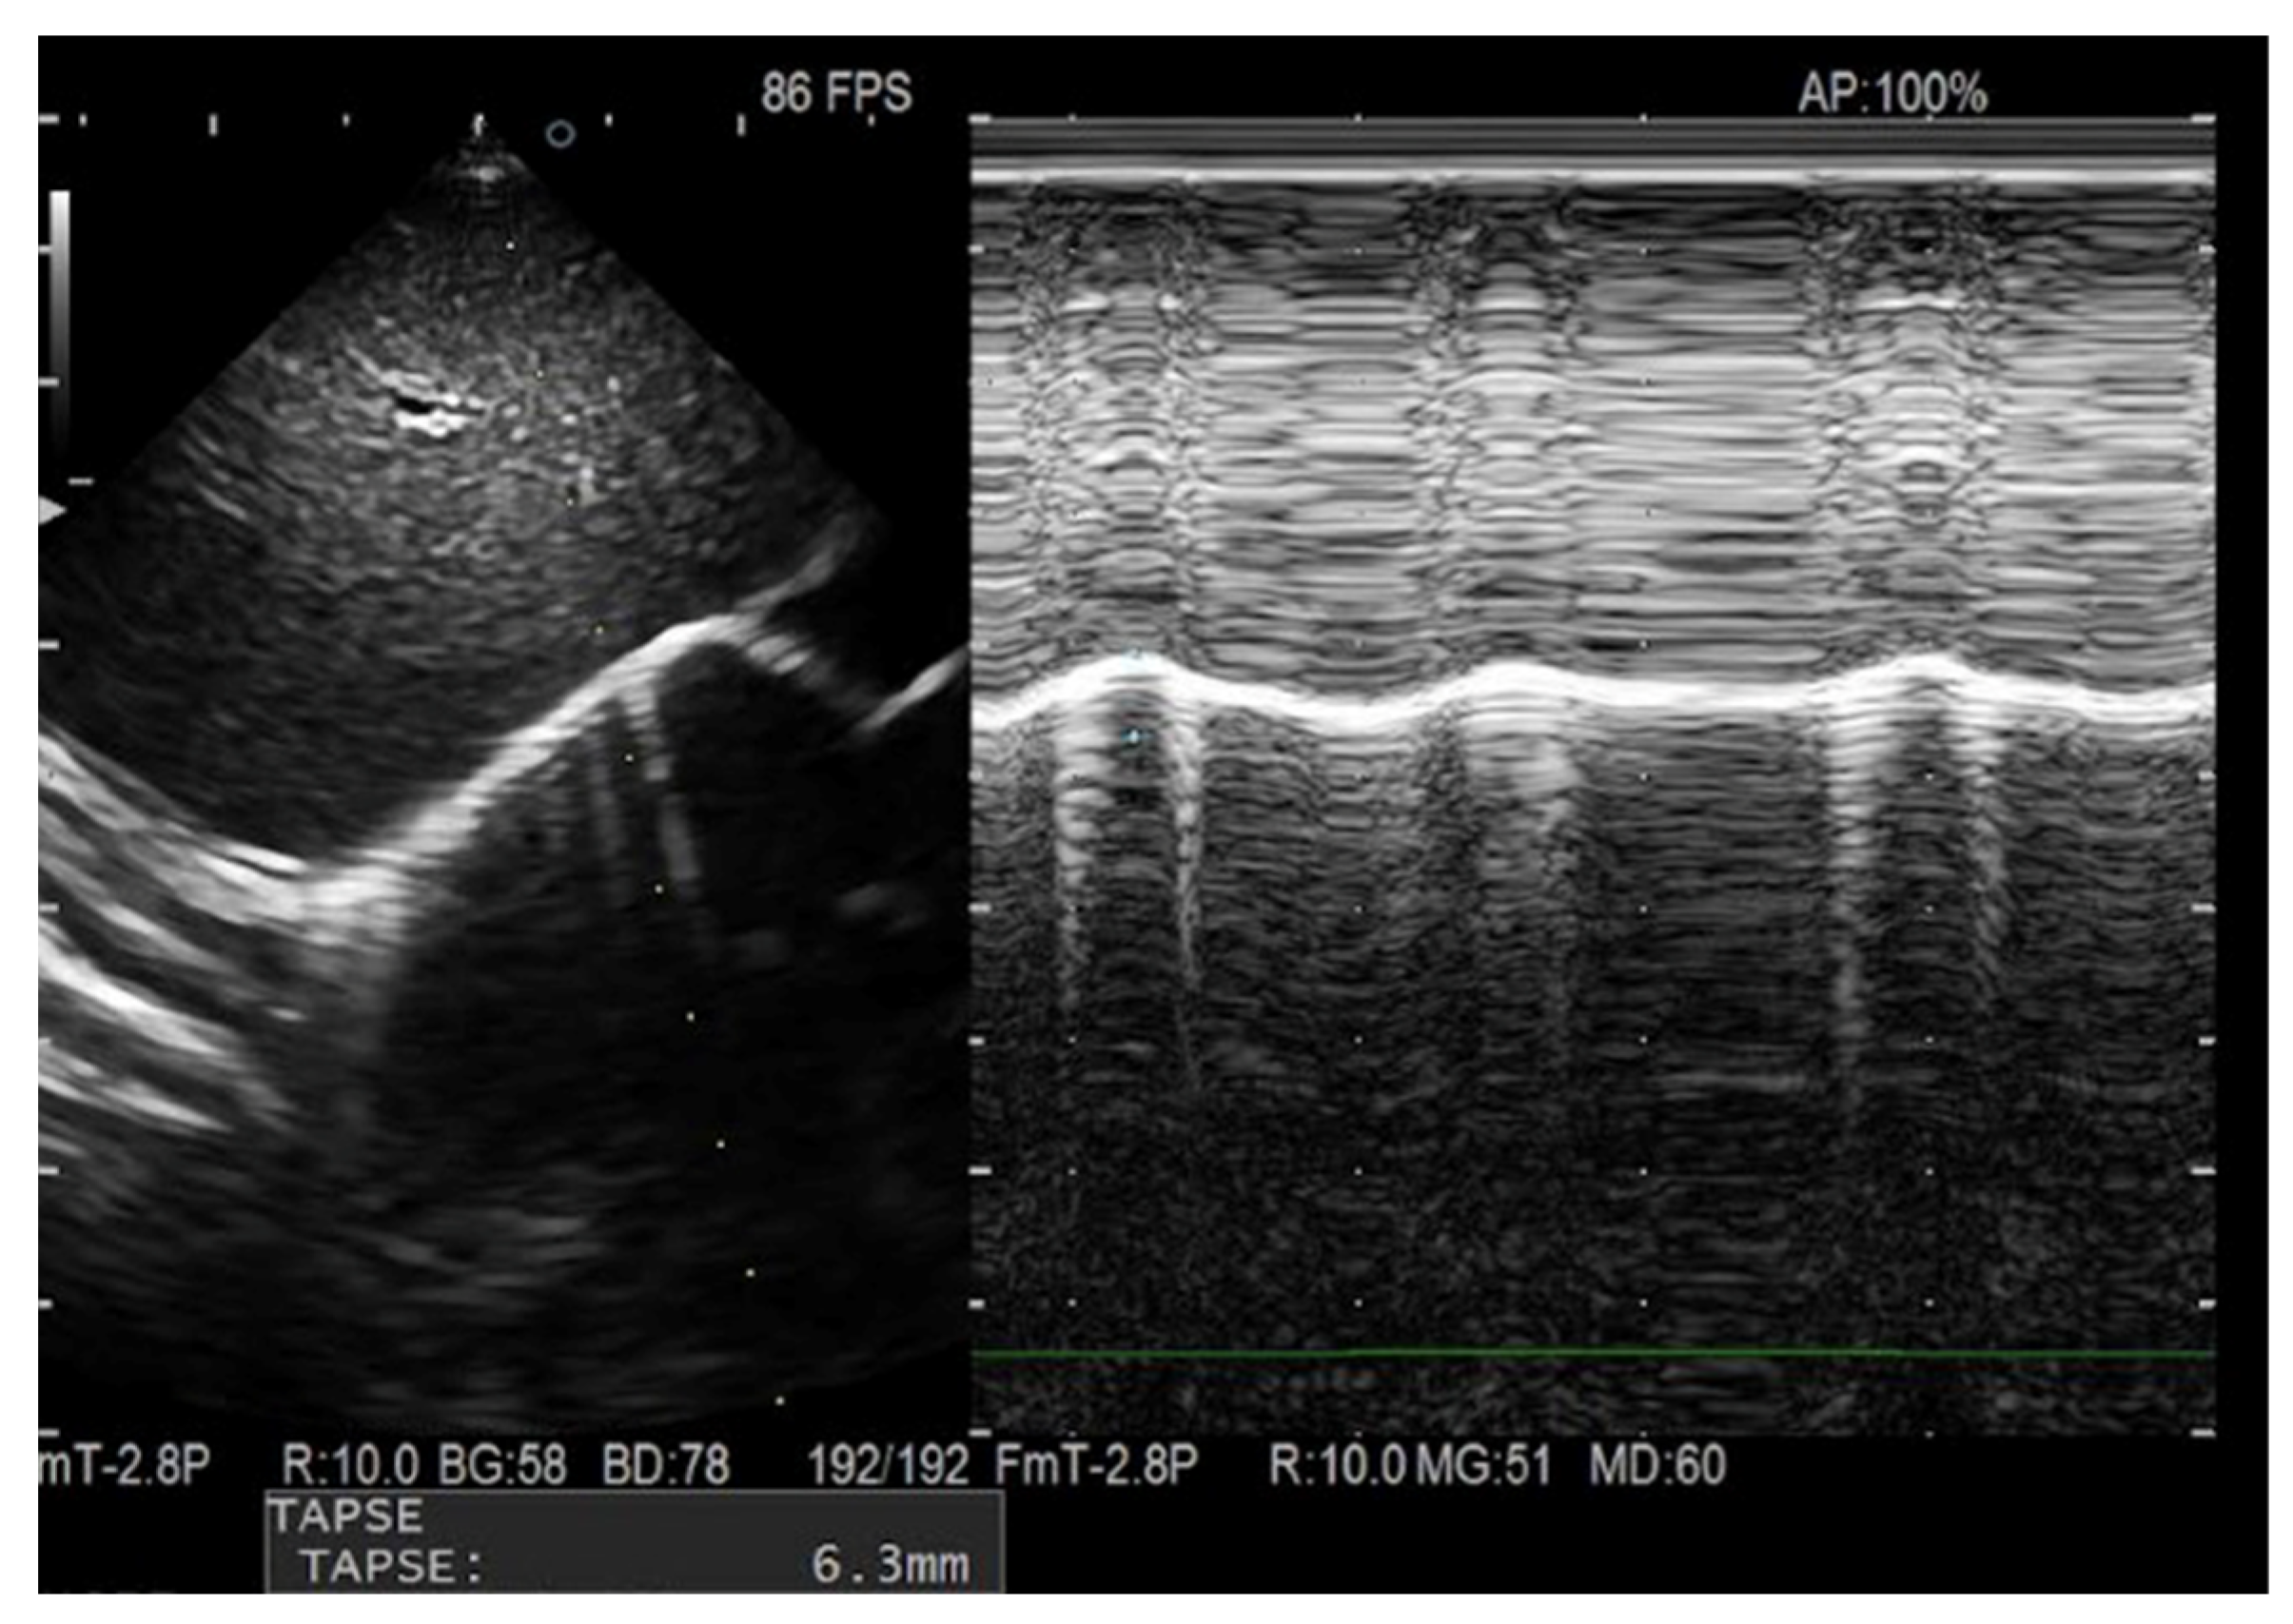

2.1. Ultrasound Equipment and Technique

2.2. Assessment of Reproducibility